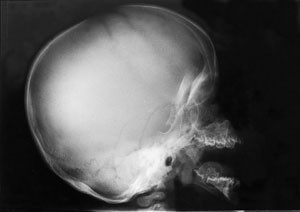

Omfattende radiologisk utredning ble rekvirert. Røntgen av kraniet viste et relativt stort nevrokranium (fig 2) med sannsynlig fortykket calvarium i basale deler. Røntgen av columna viste en kyfotisk knekk på torakolumbalovergangen (fig 3). Røntgen av bekken viste dysplastiske hofter bilateralt (fig 4). Røntgen av håndledd viste forandring av metakarpene. Røntgenologenes endelige konklusjon var dysostosis multiplex, forenlig med Hurlers syndrom. Undersøkelse hos øyelege styrket denne mistanken ytterligere, da det ble funnet bilateral, diffus tilsløring av hornhinnene. Plastisk kirurg bekreftet at det forelå triggerfinger på høyre hånds 4. finger, et typisk funn ved Hurlers syndrom.